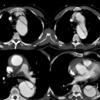

Ao Diss 2a

Date: 12/31/2004

Views: 3718